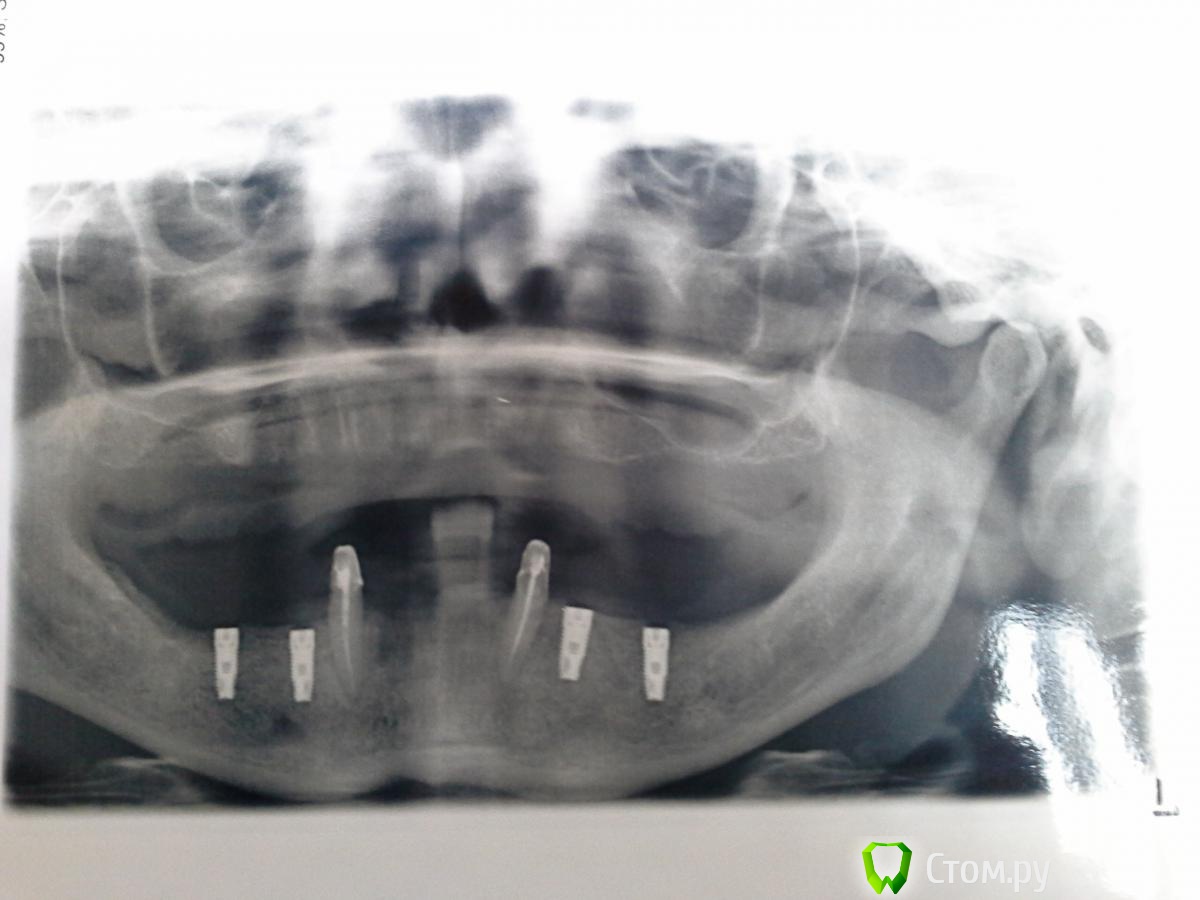

Magomed Опубликовано 3 сентября, 2014 Поделиться Опубликовано 3 сентября, 2014 (изменено) работу делал год. в.ч.удалил 8 з. низ 6 з. в.ч. каркас фрезеров. низ литьё. Изменено 3 сентября, 2014 пользователем Magomed Ссылка на комментарий

Magomed Опубликовано 5 сентября, 2014 Автор Поделиться Опубликовано 5 сентября, 2014 Здравствуйте, сколько прошло от момента имплантации верх и них и от протезирования верх и низ?низ 8 мес. верх 2 нед. протезирования Ссылка на комментарий